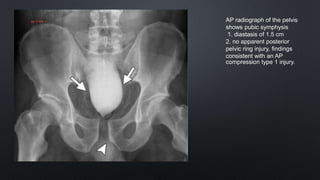

AP radiograph of the pelvis

shows pubic symphysis

1. diastasis of 1.5 cm

2. no apparent posterior

pelvic ring injury, findings

consistent with an AP

compression type 1 injury.